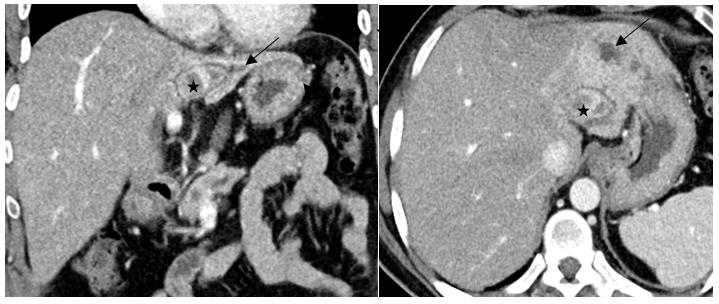

Ultrasonography showed a suspicious left hepatic duct stone with a dilated common bile duct and left biliary radicals. A contrast enhanced computed tomography scan of the abdomen and pelvis demonstrated an atrophic left lobe with multiple hypodense liver lesions suggestive of stones, particularly in segments II and III, with the largest measuring approximately 4 cm, likely representing a liver abscess with a cluster sign due to recurrent pyogenic cholangitis (Figure 1). MRCP confirmed evidence of a dilated left intrahepatic bile duct with multiple stones, associated with edema of the left liver lobe, findings consistent of oriental cholangiohepatitis. The common bile duct was dilated with multiple small stones (Figure 2). Patient underwent ERCP using Spyglass that failed to opacify the Left IHBR by to complete obstruction of the LHD due to giant stone. CBD clearance was performed with plastic stent insertion (Figure 3).

Figure 1. Axial and Coronal portal venous phase CECT showing a large stone in a peripheral segment II duct (star), which is dilating and causing obstruction of the duct and dilatation of the segmental duct distal to the stone (arrow).